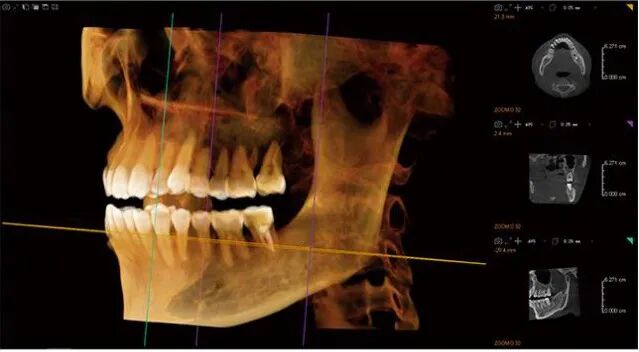

D14X10H大视野,可满足牙科临床的所有需求

一次扫描就可获得全牙列包括颞下颌关节的影像

即:单次投照即可满足口腔诊所100%的CT应用需求,种植、正畸、牙体牙髓、口外,医生不必再为想看而看不见烦恼,数字化加工中心也不必为想做而不能做遗憾。